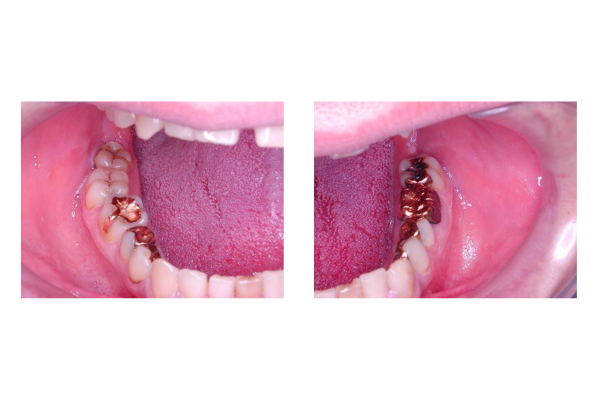

口腔外科治療

口腔外科治療では、歯や顎に関連する幅広い治療を行っています。通常の抜歯から親知らずの抜歯まで対応可能です。外傷に対しては整復固定や膿の切開なども行い、炎症の緩和を目的とした治療を実施します。特に親知らずの抜歯は歯の位置や形状によって難易度が異なるため、慎重な判断と技術が求められます。また、外傷に伴う顎の整復固定では、患者様の生活に支障が出ないよう迅速かつ適切な処置が重要です。

治療の際、痛みや腫れの程度に応じて薬剤を使用します。薬剤はすべて院内でお渡しし、治療後の経過観察も大切にしております。手術が必要な場合も、原田歯科クリニックでは幅広い手術に対応しておりますので、患者様の安心を第一に考え、治療を進めています。口腔外科治療は症状に応じて様々な方法がありますが、患者様一人ひとりに合わせた最適な治療計画を立てることが原田歯科クリニックの方針です。